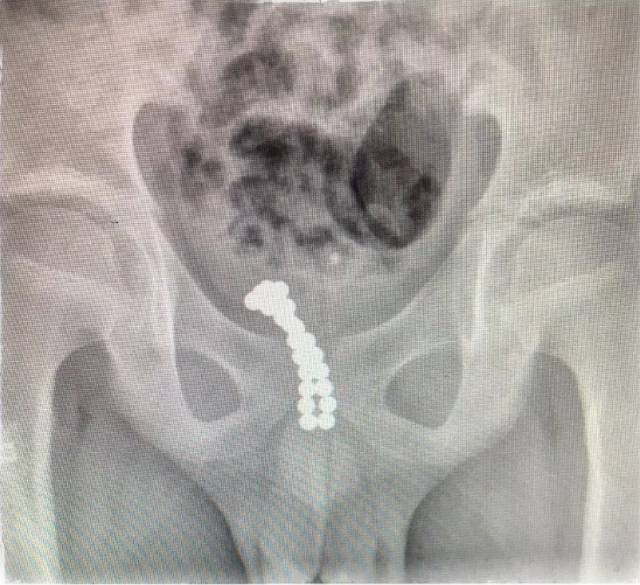

X光片显示,皮皮往体内塞入了二十几颗珠子。

了解情况后,医生安排皮皮做了X光检查。检查结果让医生大吃一惊——皮皮的体内有20多颗珠子一样的异物吸附在一起,其中十几颗进入了膀胱,另外有几颗卡在尿道口。随后,皮皮被转到温医大附二院小儿外科进一步治疗。

王永飚介绍,切开膀胱后,他看见里面有10多颗磁珠,另外有七八颗珠子牢牢地卡在皮皮的后尿道处。一般11岁孩子的尿道直径在5毫米左右,而珠子直径为3毫米,进入体内之后两个一组吸在一起,也就是说6毫米的异物卡在了尿道处,引起了尿道的肿痛、流血。最终,医生共取出了26颗。